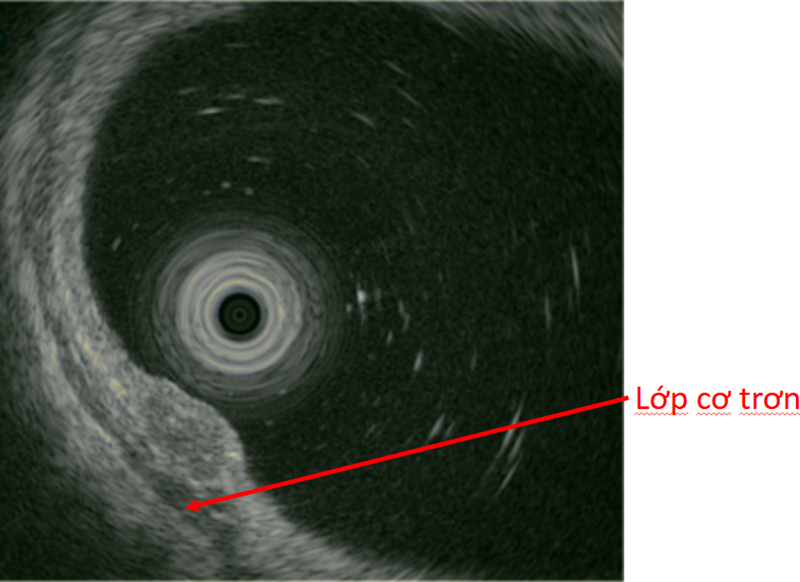

Khối u tại đại tràng dưới hình ảnh nội soi siêu âm

Để đánh giá chính xác hơn về đặc điểm và mức độ xâm lấn của khối u, bác sĩ đã tiến hành nội soi siêu âm. Hình ảnh trên nội soi siêu âm cho thấy, khối u có kích thước khoảng 0,8cm, giảm âm không đồng nhất, nằm ở lớp dưới niêm mạc, lớp cơ trơn còn nguyên vẹn.